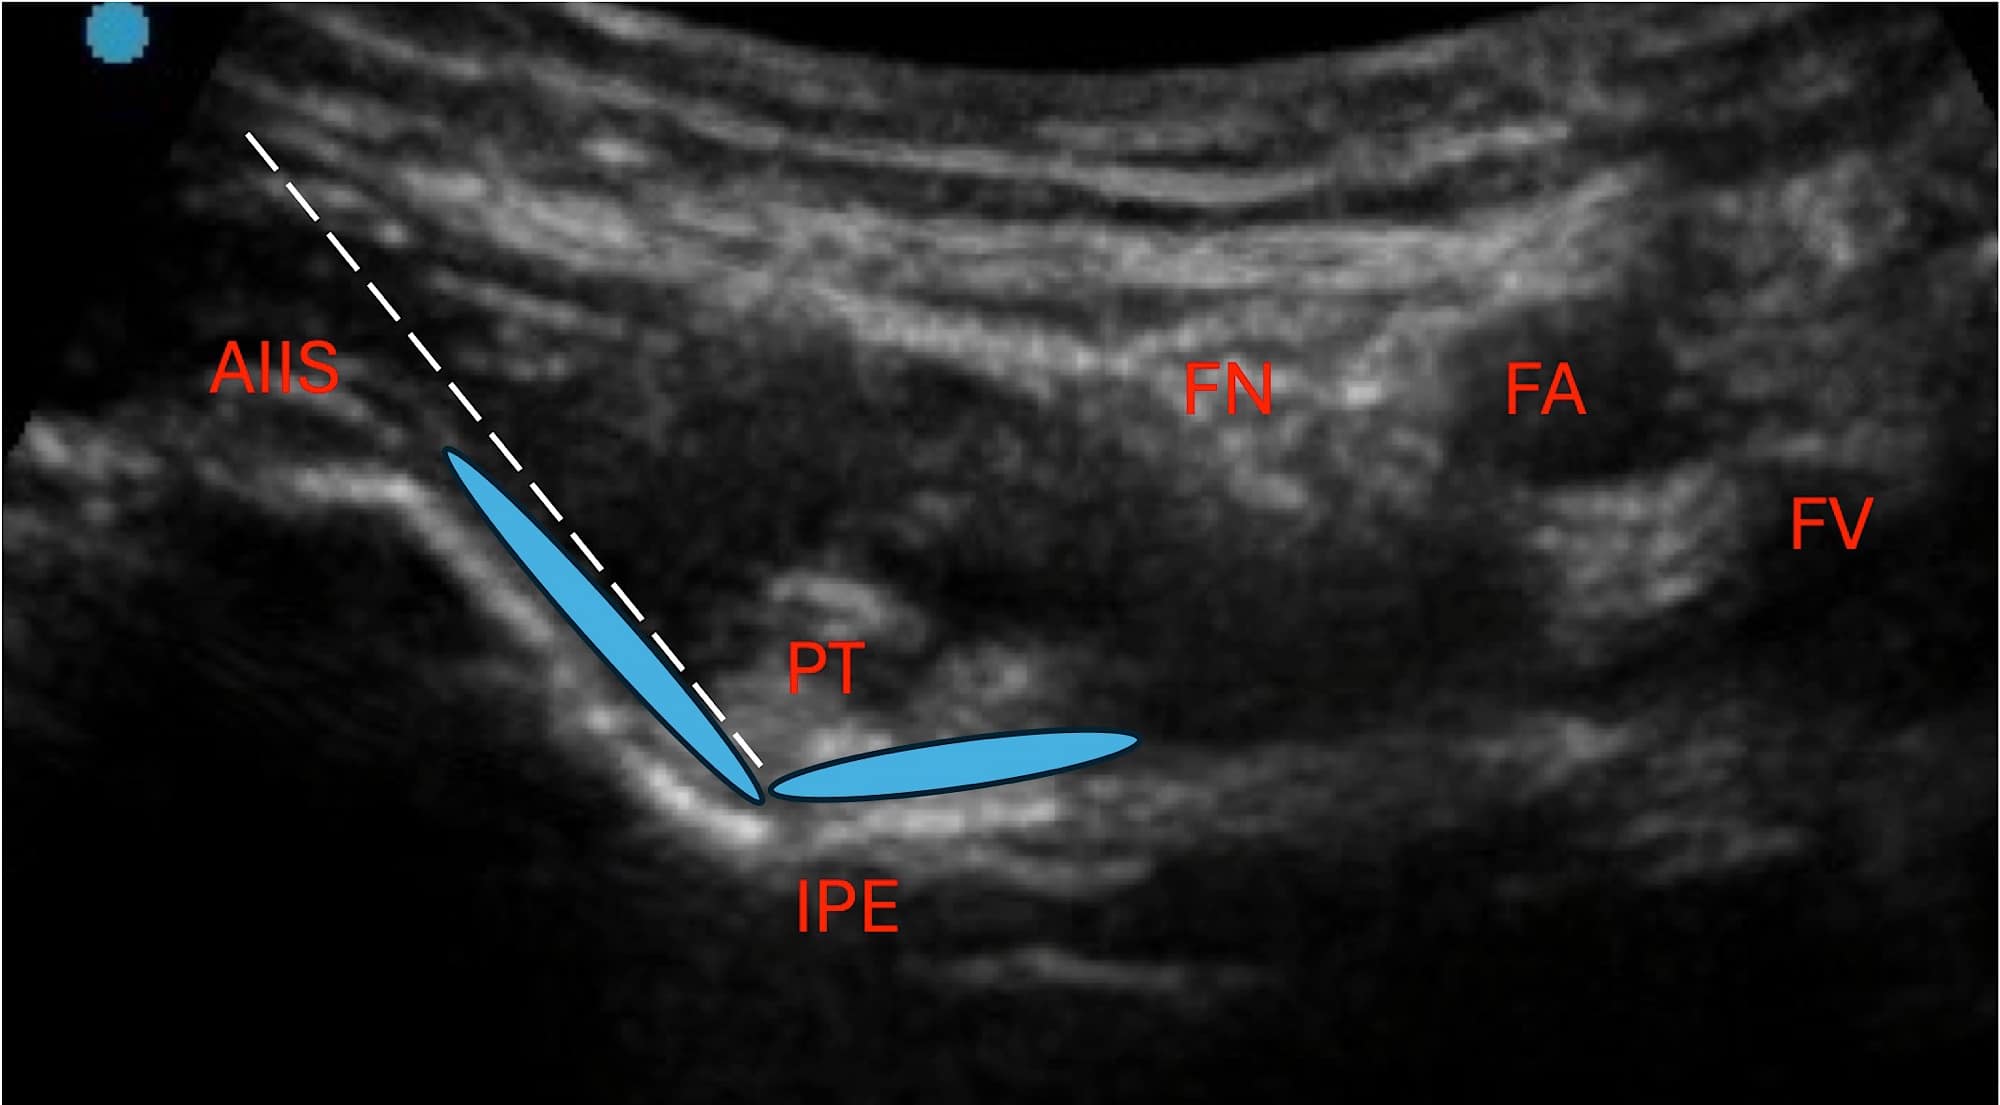

The targets of the articular branches of the femoral nerve, accessory obturator nerve, and obturator nerve are well established on ultrasound.4 Sonographically, the reliably targeted articular branches of the femoral nerve traverse between the inferior and medial portion of the anterior inferior iliac spine (AIIS) and along the iliopubic eminence (IPE). A suggestion for the radiofrequency (RF) cannula entry point being 1-2 cm lateral to the femoral artery has been made in the literature; however, it has been the authors’ experience to insert the RF cannula just medial to the AIIS and along the same angle as the bony descent from the AIIS to the IPE.6 This approach allows for improved angulation to place the needle deep to the psoas tendon without piercing the structure.

AIIS = anterior inferior iliac spine, PT = psoas tendon, IPE = iliopubic eminence, FN = femoral nerve, FA = femoral artery, FV = femoral vein

Sequential lesion along the target zone can also be performed easily by withdrawing the RF cannula more proximally. The articular branches of the accessory obturator nerve are also best targeted along the IPE and are typically captured via the lesioning approach described for the articular branches of the femoral nerve. The target for the articular branches of the obturator nerve can be visualized along the inferomedial acetabulum (IMA). This view is typically first achieved through the hip intra-articular view sonographically. The probe is then translated inferomedially to visualize the inferomedial acetabulum.

IPE = iliopublic eminence, FA = femoral artery

Benefits of ultrasound use in hip denervation include improved visualization of the vasculature, neural, and important musculoskeletal structures when traversing the needle towards the target zone. In targeting the IPE where the articular branch of the femoral nerve and the accessory obturator nerves lie, care should be taken to avoid RF cannula puncture of the psoas tendon, which otherwise may result in injury of the tendon and significant post-procedure pain (see Figure 2).6 In targeting the inferomedial acetabulum where the articular branches of the obturator nerve lie, care should be taken to avoid RF cannula through the femoral artery and femoral nerve as well as adjacent vasculature, such as the external pudendal artery.6 Although the rates of femoral artery and nerve injuries are not well known for hip denervation, a sonographic approach serves to reduce the risks of inadvertent injury (see Figure 3).